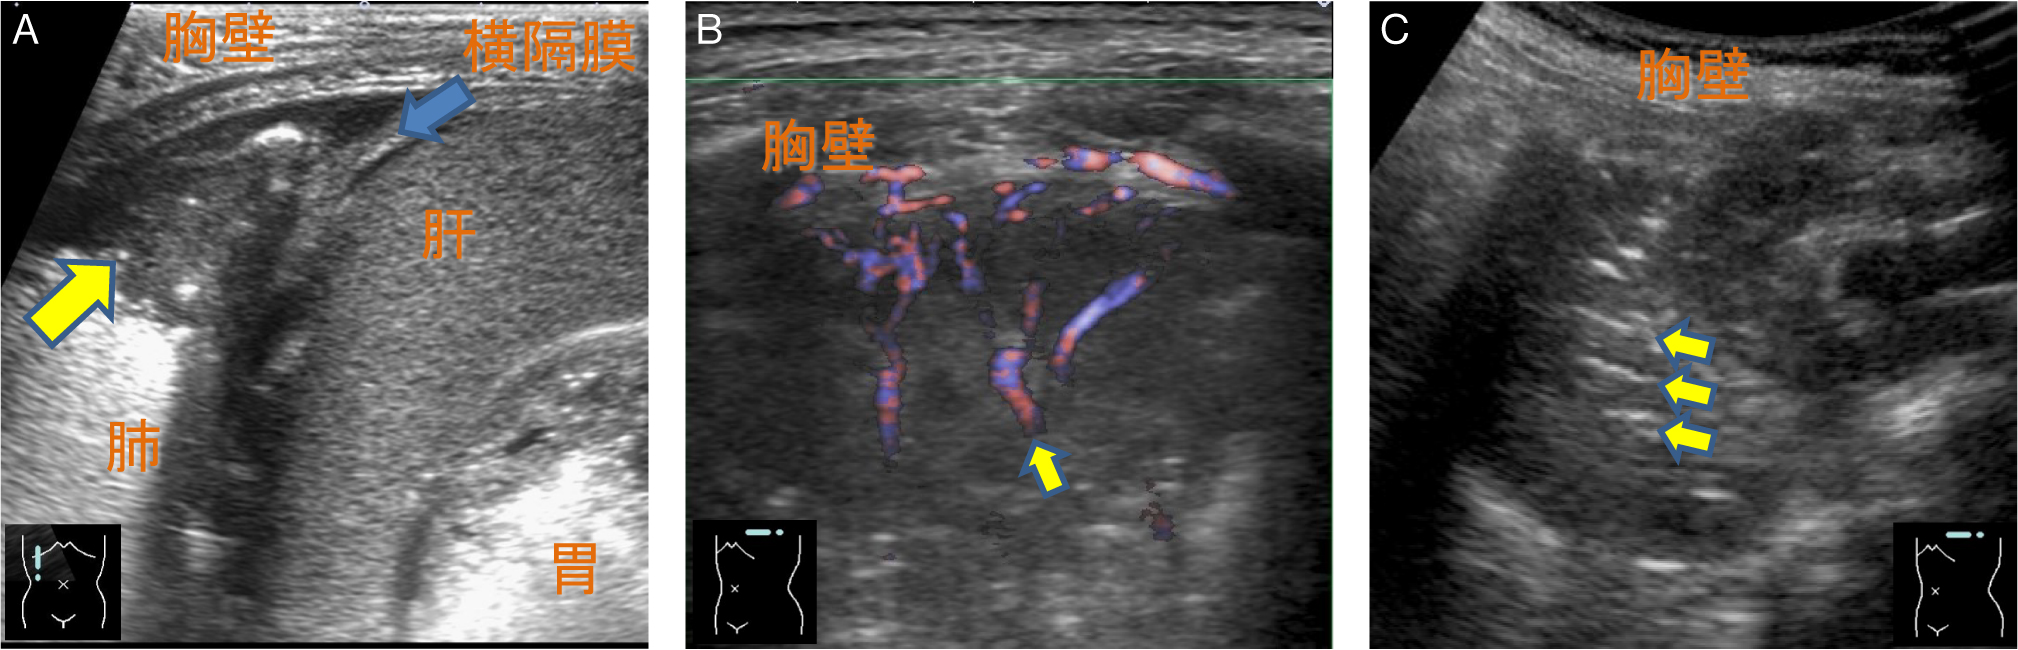

胸腔を観察するにはまず横隔膜,肝臓,脾臓,胸膜を確認するが,胸水が貯留している場合,正常で見られるはずのcurtain signは消失し,胸水は胸腔内の無エコー域として描出される(Fig.11).Mモードで確認できるsinusoid signや,貯留した胸水を通して脊椎が横隔膜より頭側でも描出されるspine sign(Fig.11)も併用して診断できる.

通常脊椎は腹腔内の実質臓器経由でしか観察できないが,胸水貯留があると胸水を介して横隔膜より頭側でも観察できる(→:spine sign).

膿胸の際の胸腔内液体貯留は,胸水が低輝度を示すのに対して,相対的に高輝度を示す.その他の所見として,細胞性沈澱物を伴う,被包化される傾向にある,隔壁形成が目立つ,重力に抗した分布,胸膜肥厚を合併するなどの傾向がある(Fig.12A).しかし肺炎随伴胸水との鑑別は,超音波所見のみからは困難な場合が多い.胸膜外膿瘍とは壁側胸膜の位置により鑑別可能である(Fig.12B).

A:臓側胸膜と壁側胸膜の間に不均一な高輝度を呈する液体貯留が認められる(→).背側には細胞成分を示唆する沈澱物が認められる(☆).胸壁外膿瘍(B→)とは胸膜の位置(*)で鑑別可能であり,この部分でlung slidingが確認できる.

含気を失った肺実質は低輝度に観察される(Fig.13A).内部には血流を有する肺動脈と肺静脈が描出され,カラードプラやパワードプラなどの血流イメージで明瞭となる(Fig.13B).旧来の機器では肝臓様(hepatization)あるいは組織様(tissue-like)と例えられた.内部に含気を有する気管支は高輝度構造として描出され,air bronchogramと表現される(Fig.13C).分泌物などが貯留して含気がない場合には,fluid bronchogramと呼ばれる.

A:肋骨横隔膜角の肺野が含気を失って低輝度に描出され(→),内部の構造が認識可能である.中枢側の肺野には含気が認められる.B:血流イメージで肺動脈と肺静脈が描出される.C:気管支内部には含気があり,高輝度に描出される(→:air bronchogram).